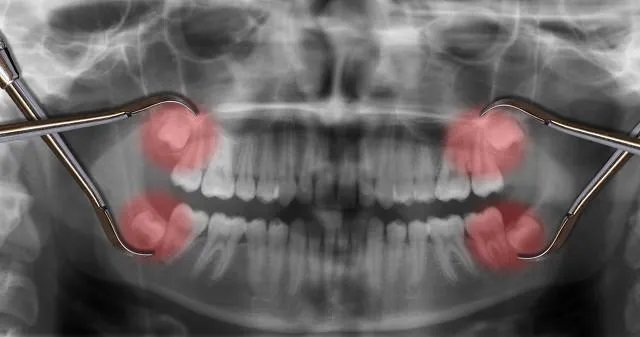

下颌角肥大和咬肌发达,脸都会显得又大又宽。所以,通过下颌角截骨手术和下颌骨磨削手术,还有针对咬肌的瘦脸针可以实现改变脸宽和脸型的效果。

传说中的削骨磨腮长这样:

磨骨手术:磨骨手术是通过去掉一部分腮骨,从而改变脸型的一种手术。

削骨手术:多余下颌骨内、外两层全部切除,再对余下颌骨外板的边缘继续打磨变薄从而瘦脸的整形手术。